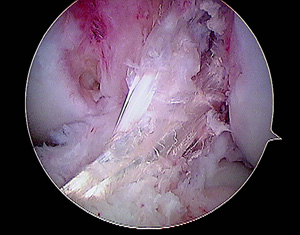

En todos los pacientes de ésta muestra fueron evaluadas radiografías y RMI para determinar las causas de la falla, dividiéndo a los pacientes en 2 grupos en virtud de si las cirugía primaria había sido efectuada por nuestro grupo de trabajo ó por otro. La causa más frecuente de fracaso en nuestra muestra fue el error técnico (75,8%), correspondiendo sólo el 46,8% a un túnel femoral anterior y el 28,5% a un túnel tibial posterior. (Figs.1, 2 y 3)

Figura 2: RMI Corte sagital. Combinación de túneles femoral y tibial anteriores. |